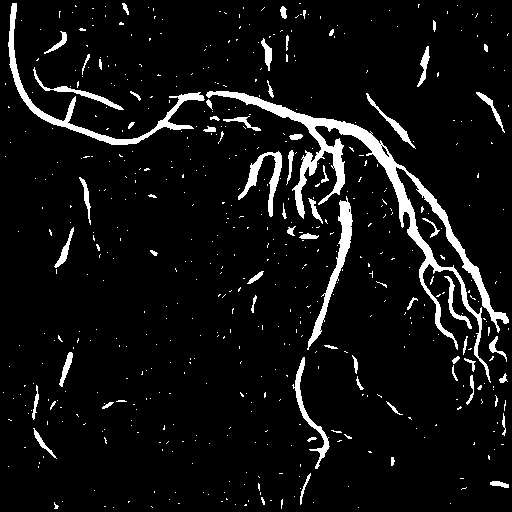

4.1 XACV Dataset

We collect 111 complete records of coronary artery X-ray videos, encompassing the injection, flow through the blood vessels around the heart, and dissipation of the contrast agent. Subsequently, we establish the XACV (X-ray Angiography Coronary Video) dataset. Each video consists of varying numbers of high-resolution coronary artery X-ray images. We invite experienced radiologists to annotate the vascular regions, focusing on one or two frames where the contrast agent is most prominent in each video. The XCAD dataset contains only a single image, and the CADICA video dataset does not provide corresponding ground truth. Therefore, in the following experiments, we conduct all the analyses on our collected XACV dataset and the corresponding GT for each sequence. In Figure 5, we show that compared to other publicly available datasets, XCAD [33] and CADICA [19], our dataset exhibits finer annotations in the vascular regions, providing an advantage for future related tasks. The development and use of our dataset have been approved by our institution’s IRB.